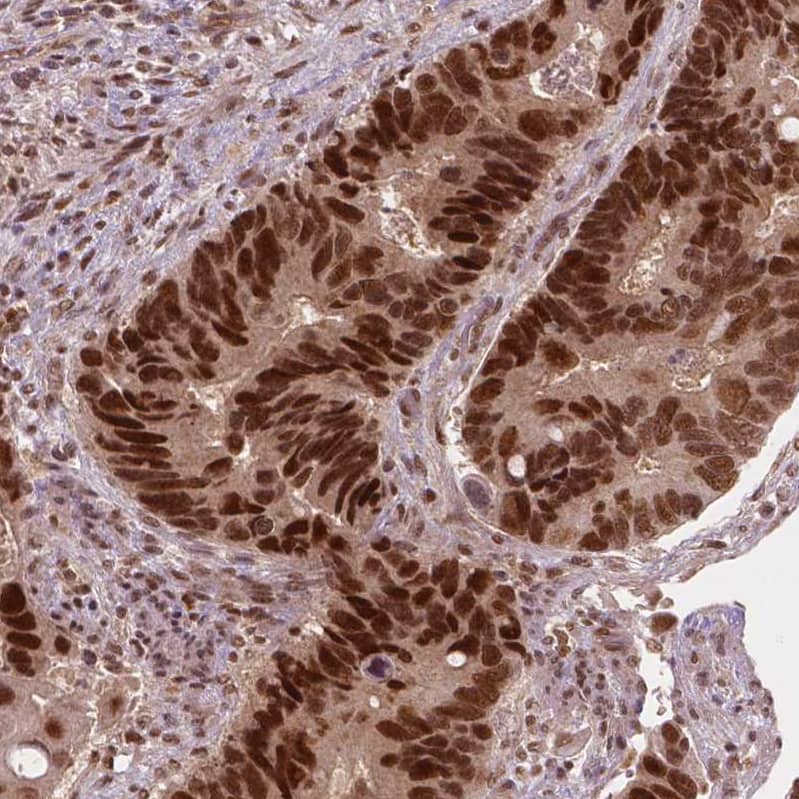

Staining of human colorectal cancer shows strong nuclear positivity in tumor cells.